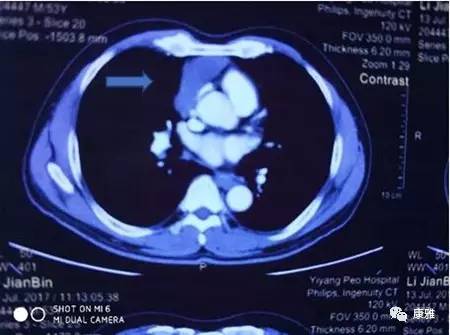

图1术前胸部CT(肿块为箭头所指处))